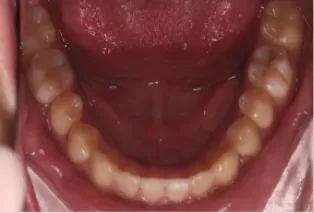

Photos intra-orales